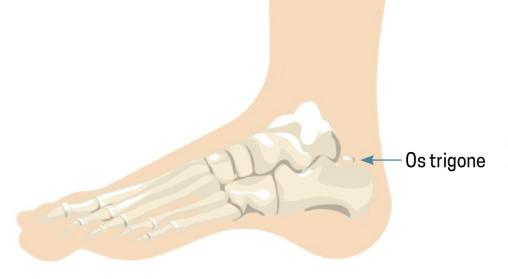

L’os trigone est un os dit surnuméraire situé derrière le talus (fig. 2). Il résulte de la non-fusion du versant postérieur du talus entre l’âge de 7 et 13 ans.1 Sa présence peut entraîner des douleurs à la flexion plantaire forcée, piégeant cet os entre le calcanéus et le tibia – c’est le syndrome de l’os trigone (fig. 3).2